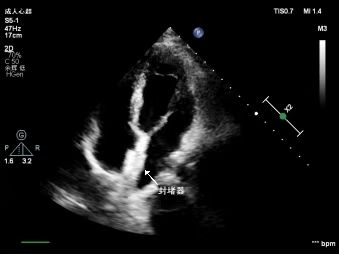

2、经食管超声心动图(TEE) 将探头经咽喉伸入食管,紧贴心脏后方,不受肺气干扰,可清晰观察到PFO的位置、形态、精确测量孔径及隧道长度,检出率高。其缺点是侵入性操作可能引发恶心,需局部麻醉。适用于疑似反常栓塞患者的金标准检查方法。

3、右心声学造影检查 目前常用振荡的无菌生理盐水配制声学造影剂,由于其产生的微泡较大,不能通过肺循环,只能在右心显影,故称为右心声学造影剂。右心声学造影检查可实时观察气泡是否从左心房出现。若存在PFO,气泡会通过未闭合的卵圆孔,直接“漏”到左心系统。TEE 结合右心声学造影能评价右向左分流量,评估患者的风险程度;可清楚观察右向左分流是来源于PFO 还是心内其他分流(见图2)。

图2 经食管超声心动图右心声学造影显示右向左分流